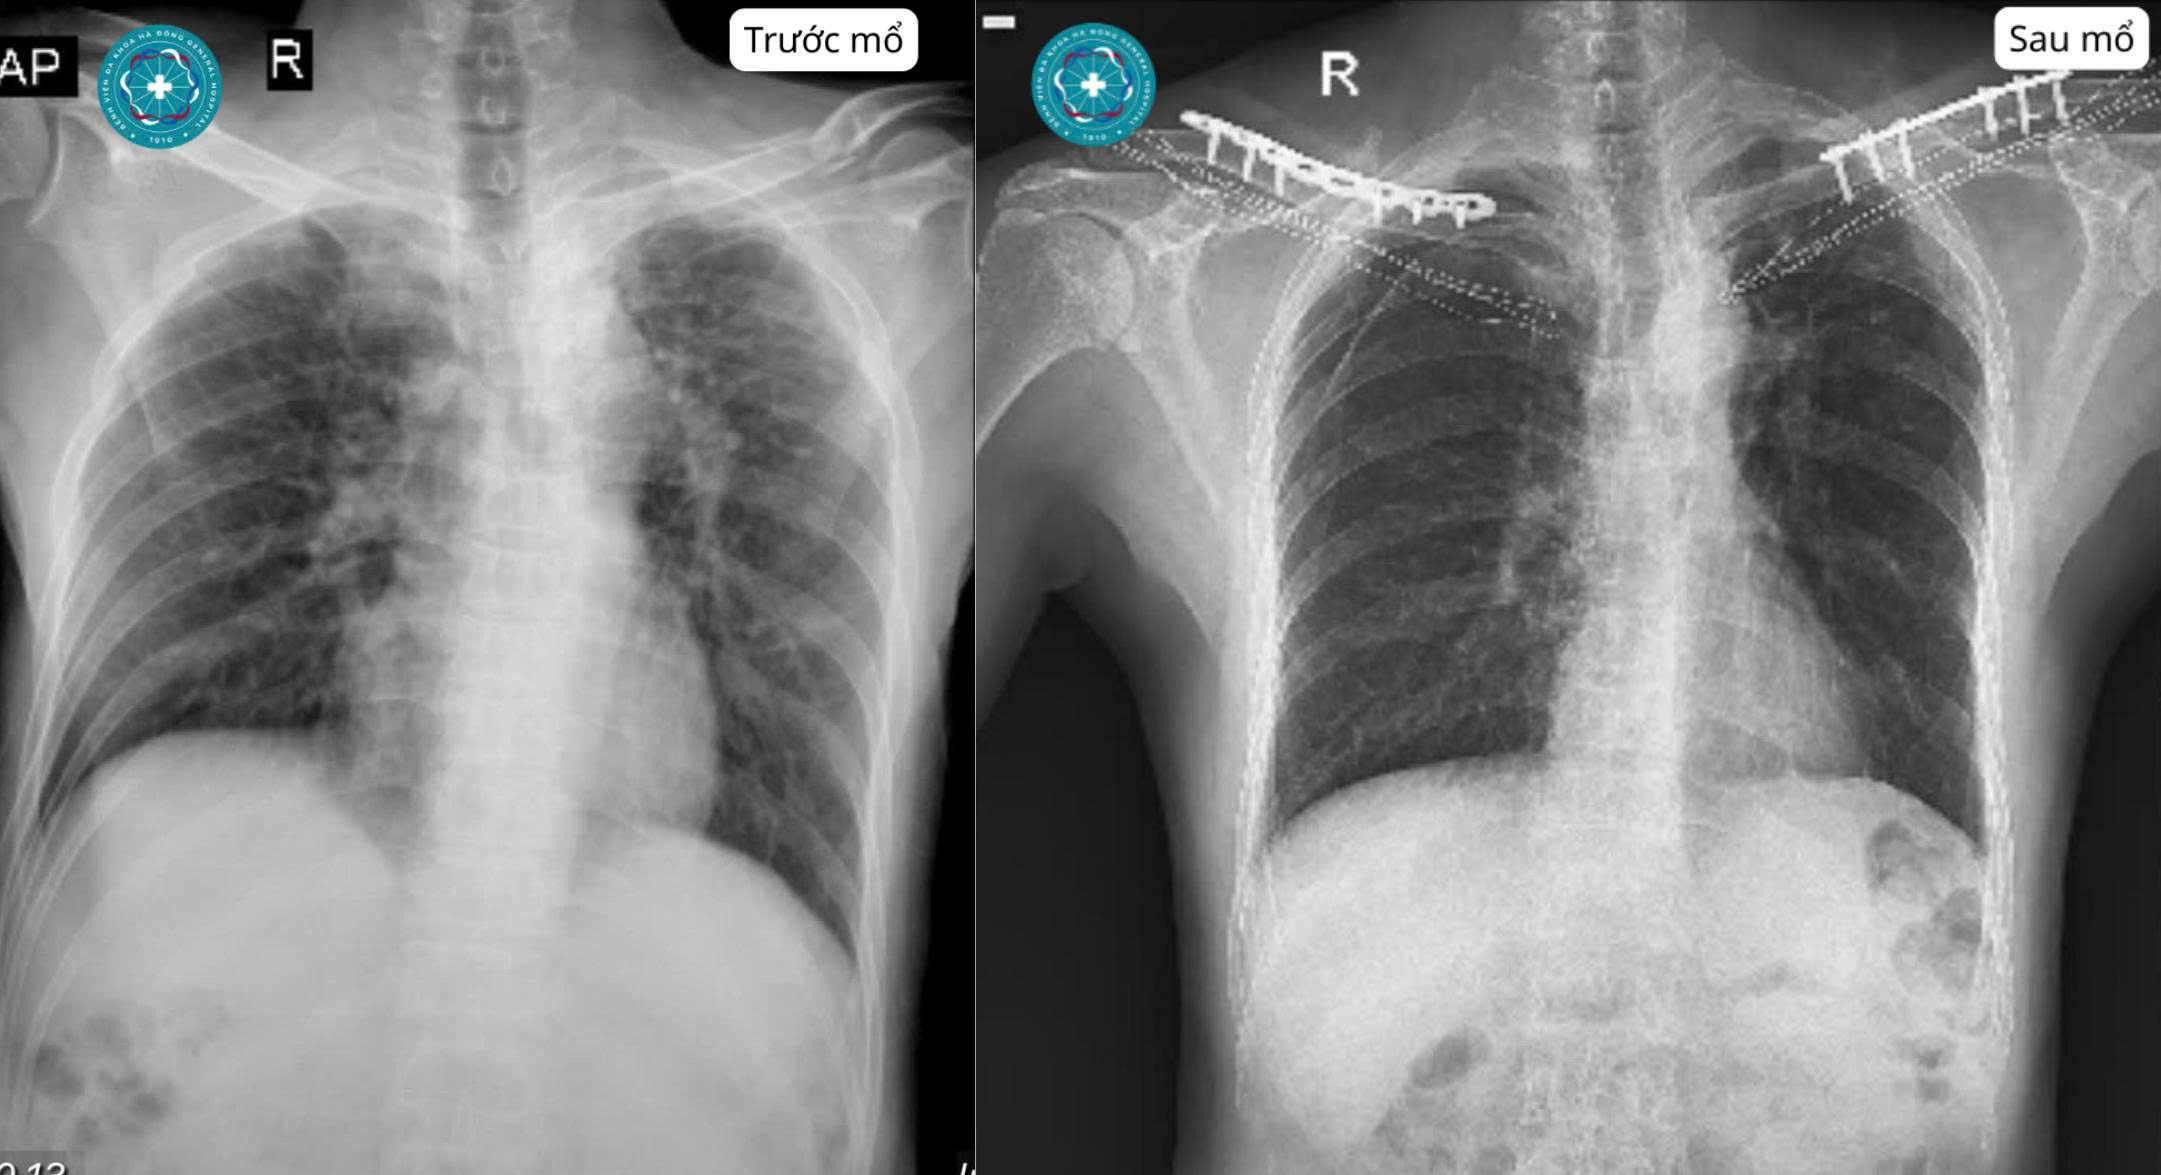

Hình X-quang trước mổ và sau mổ cho thấy tổn thương gãy xương đòn hai bên đã được kết hợp xương bằng nẹp vít. Thông tin định danh người bệnh đã được che bỏ.

Với dạng tổn thương này, điều quan trọng không chỉ là xác định ổ gãy mà còn phải đánh giá đầy đủ để tránh bỏ sót chấn thương phối hợp ở lồng ngực, cột sống cổ, khớp vai, mạch máu và thần kinh. Sau khi thăm khám, làm cận lâm sàng cần thiết và cân nhắc chỉ định điều trị, bệnh nhân được phẫu thuật kết hợp xương đòn hai bên.

Hình ảnh sau mổ cho thấy hai xương đòn đã được nắn chỉnh và cố định tương đối vững bằng nẹp vít. Vết mổ hai bên khô, mép da áp tốt. Đây là nền tảng quan trọng để người bệnh giảm đau, thuận lợi hơn cho chăm sóc sau mổ và từng bước tập phục hồi chức năng vai.